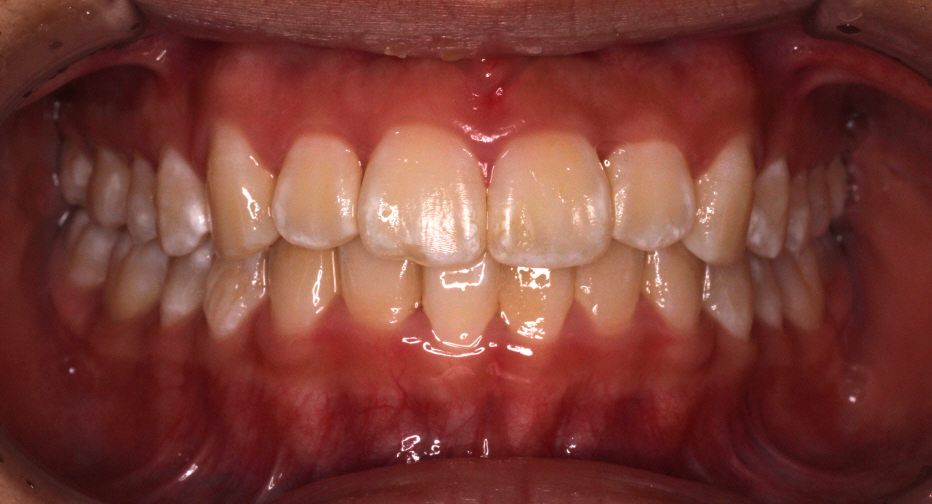

初診時の写真です。

前歯にはがたつき(叢生)がみられ、奥歯は上の歯と下の歯が1歯対1歯で噛んでいることがわかります。

つまり出っ歯の噛み合わせです。

診断:上顎前突・前歯部叢生